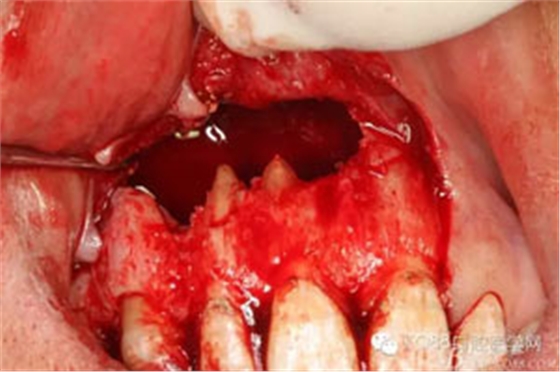

圖4.翻瓣、去除覆蓋在囊腫表面骨質(zhì),暴露出囊壁。

圖5.沿著骨壁完整剝離囊壁